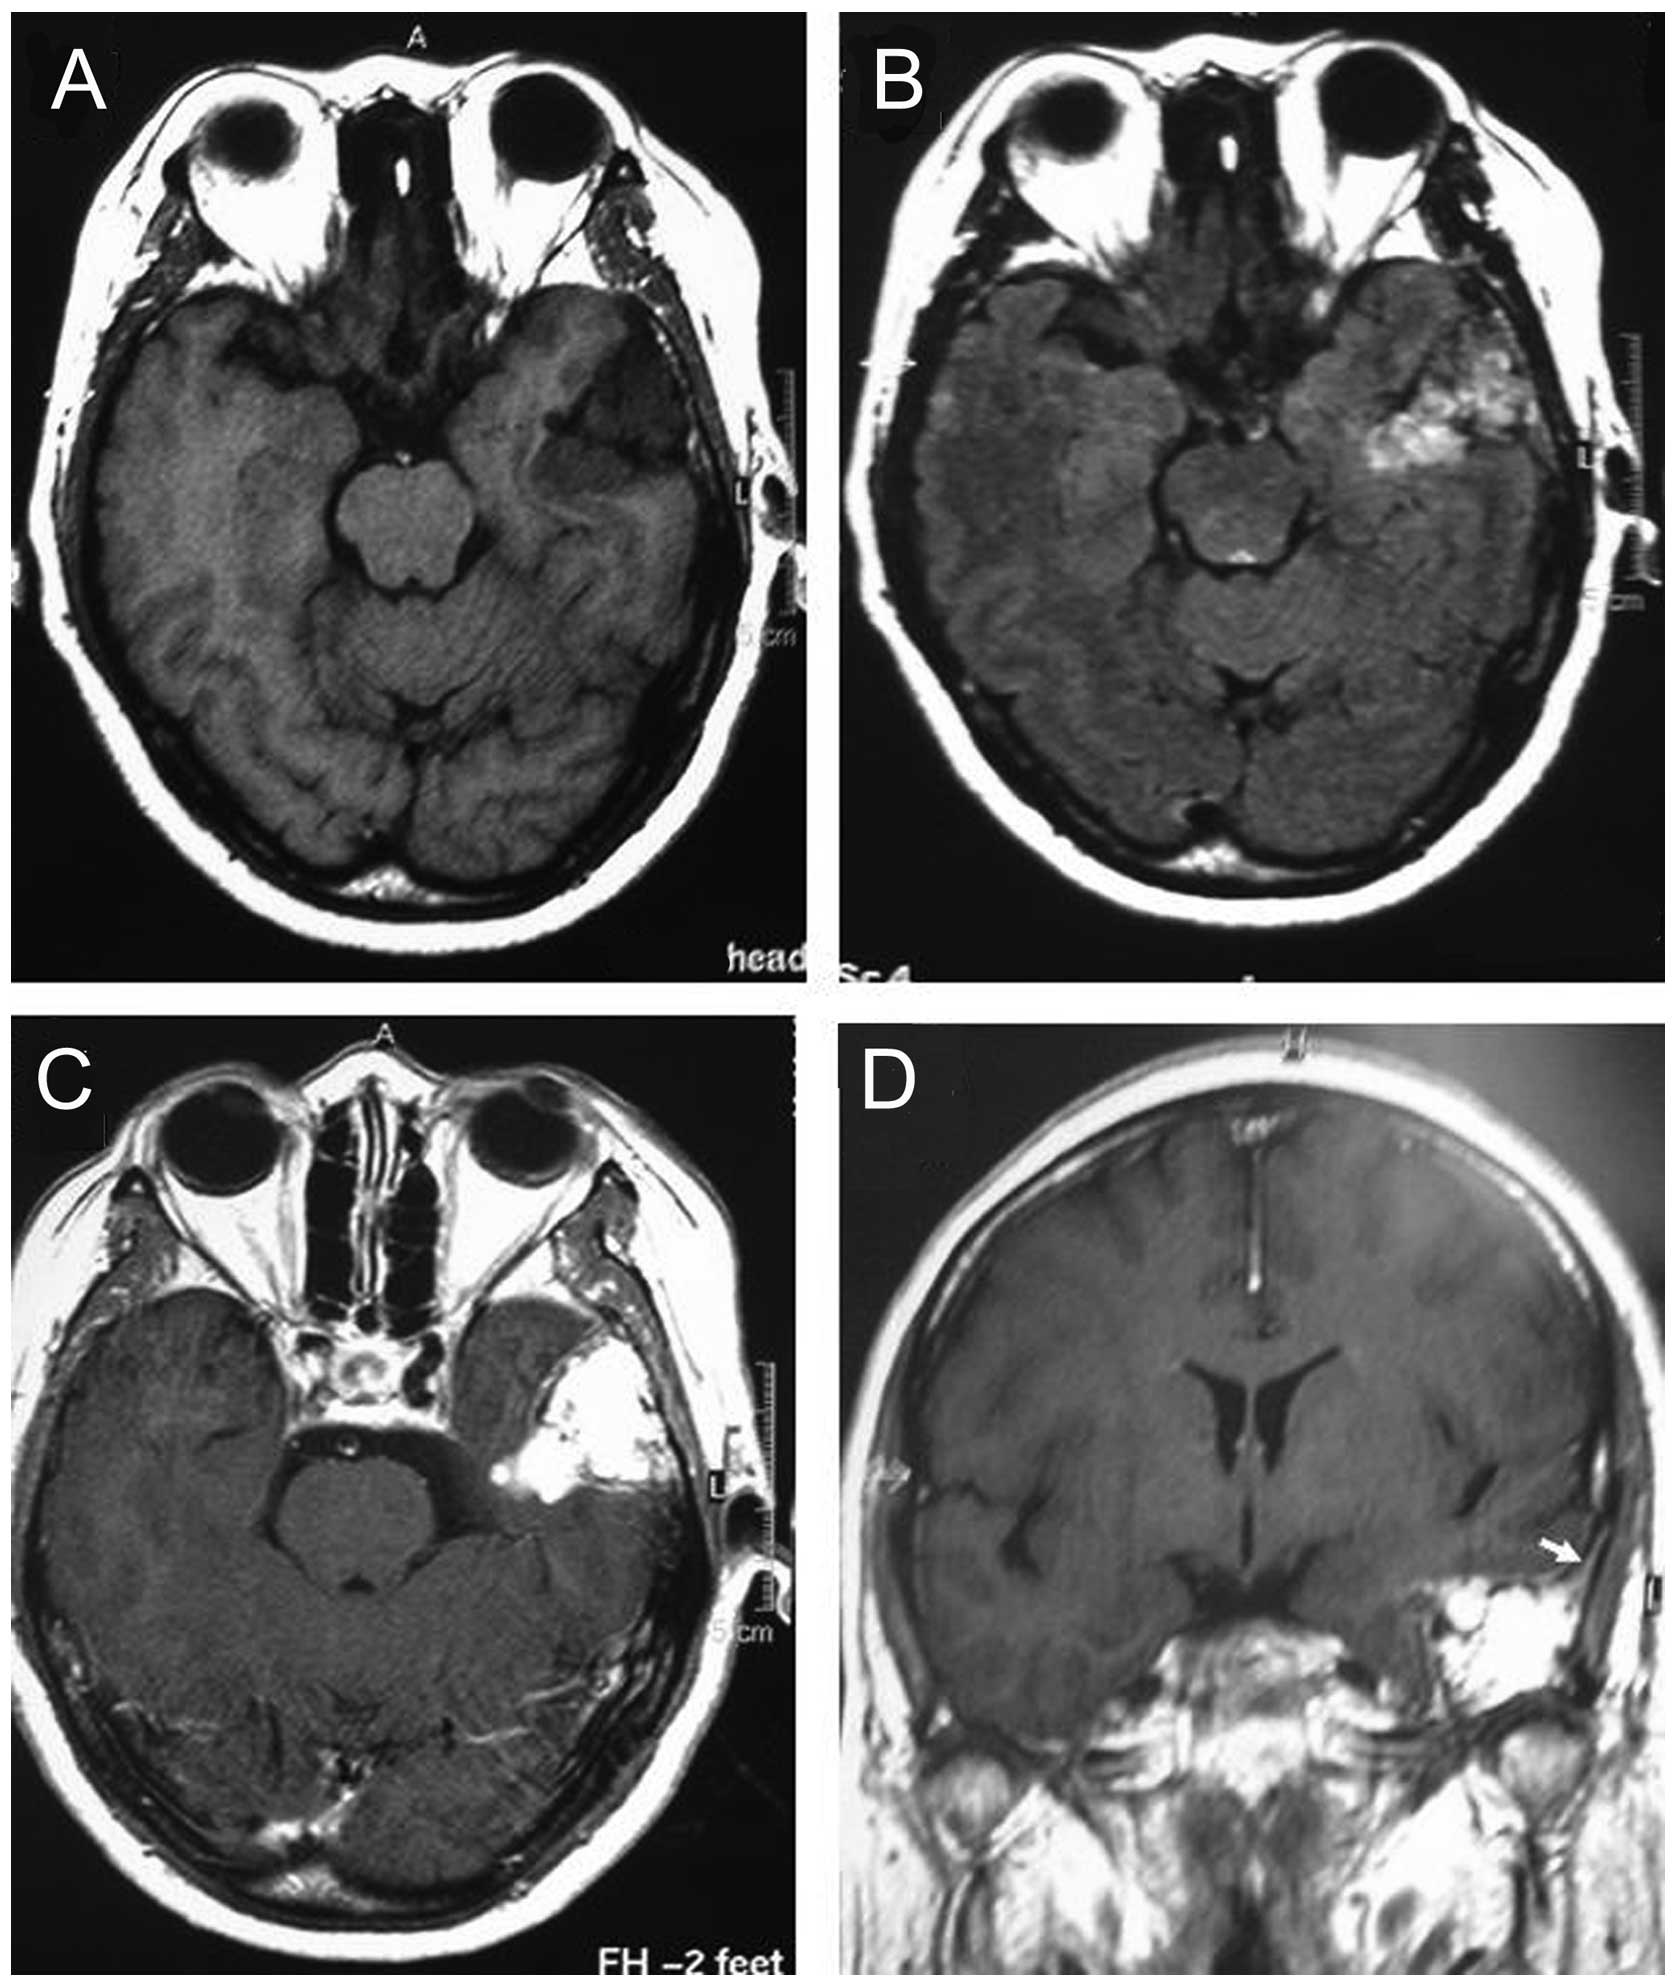

A 57-year-old female presented with pulsatile tinnitus and episodic vertigo associated with a ten-year history of intermittent faint headaches. There was no history of facial twitching or weakness. There was no evidence of facial nerve dysfunction upon physical examination. Pure tone audiometry revealed a hearing level of 28 dB on average in the right ear and a normal hearing level on the left. There was no history of trauma or neurological disturbances. Gadolinium-enhanced magnetic resonance imaging showed a mass measuring 42×36×35 mm in the right petrous bone, which was hypointense on T1-weighted images and heterogeneously hyperintense on T2-weighted images. Additionally, a dural tail sign was shown following gadopentetate dimeglumine administration (Fig. 1).

Figure 1

Magnetic resonance imaging prior to surgery. (A) Axial T1-weighted MRI revealing a hypointense lesion in the right petrous bone. (B) Axial T2-weighted magnetic resonance imaging showing the lesion to be hyperintense. (C) Axial and (D) coronal gadolinium-enhanced T1-weighted magnetic resonance imaging showing a heterogeneously enhanced lesion, with a dural tail sign (arrows).